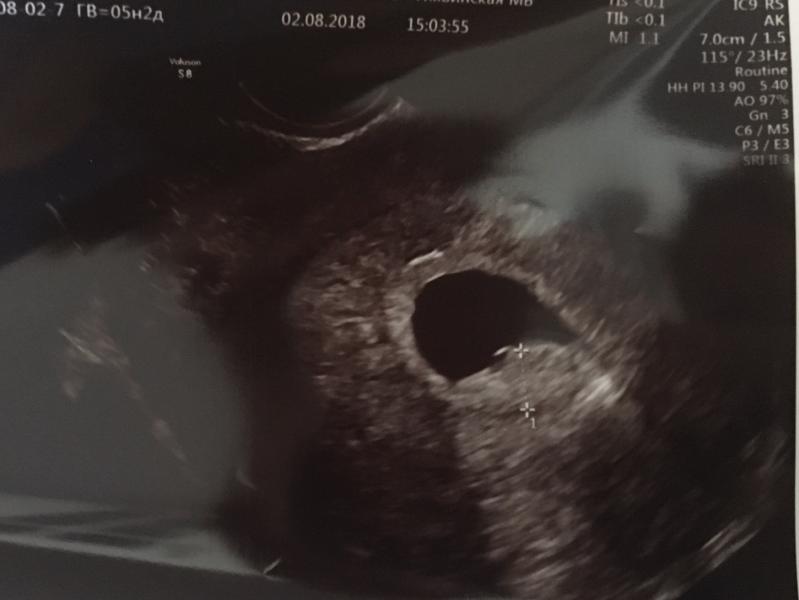

Девочки, кто разбирается или было похожее... Отправили меня на узи, чтобы подтвердить маточную беременность. На узи обнаружили утолщение стенки, что это обьяснить не смогли, повторю узи через неделю. Что это может быть?

@yulia02yulia, это да, меня беспокоит "утолщение стенки плодного яйца до 4 мм"